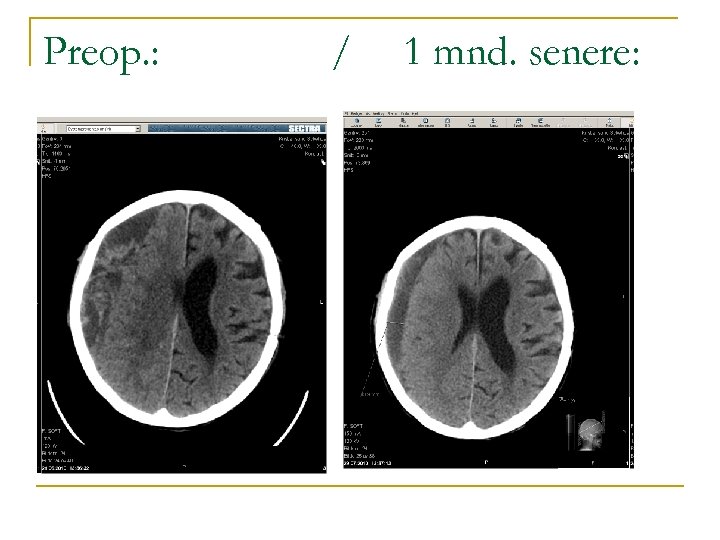

Preop. : / 1 mnd. senere:

… og slik gikk det med fru A. : n n 9. postoperative dag utskrevet til hjemmet med hjemmesykepleie. 8 mndr. etter siste operasjon bor hun på sykehjem og har en kognitiv svikt (blandingsetiologi).